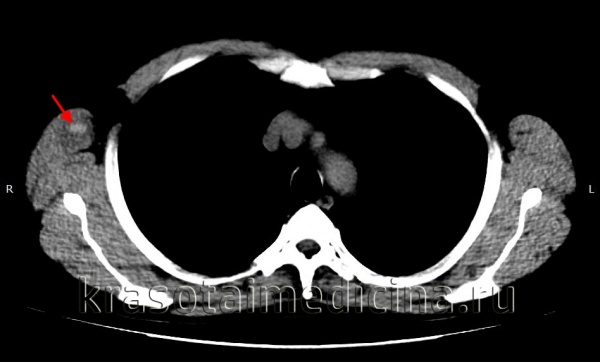

Компьютерная томография головного мозга. Гематома периферических мягких тканей левой теменной области.